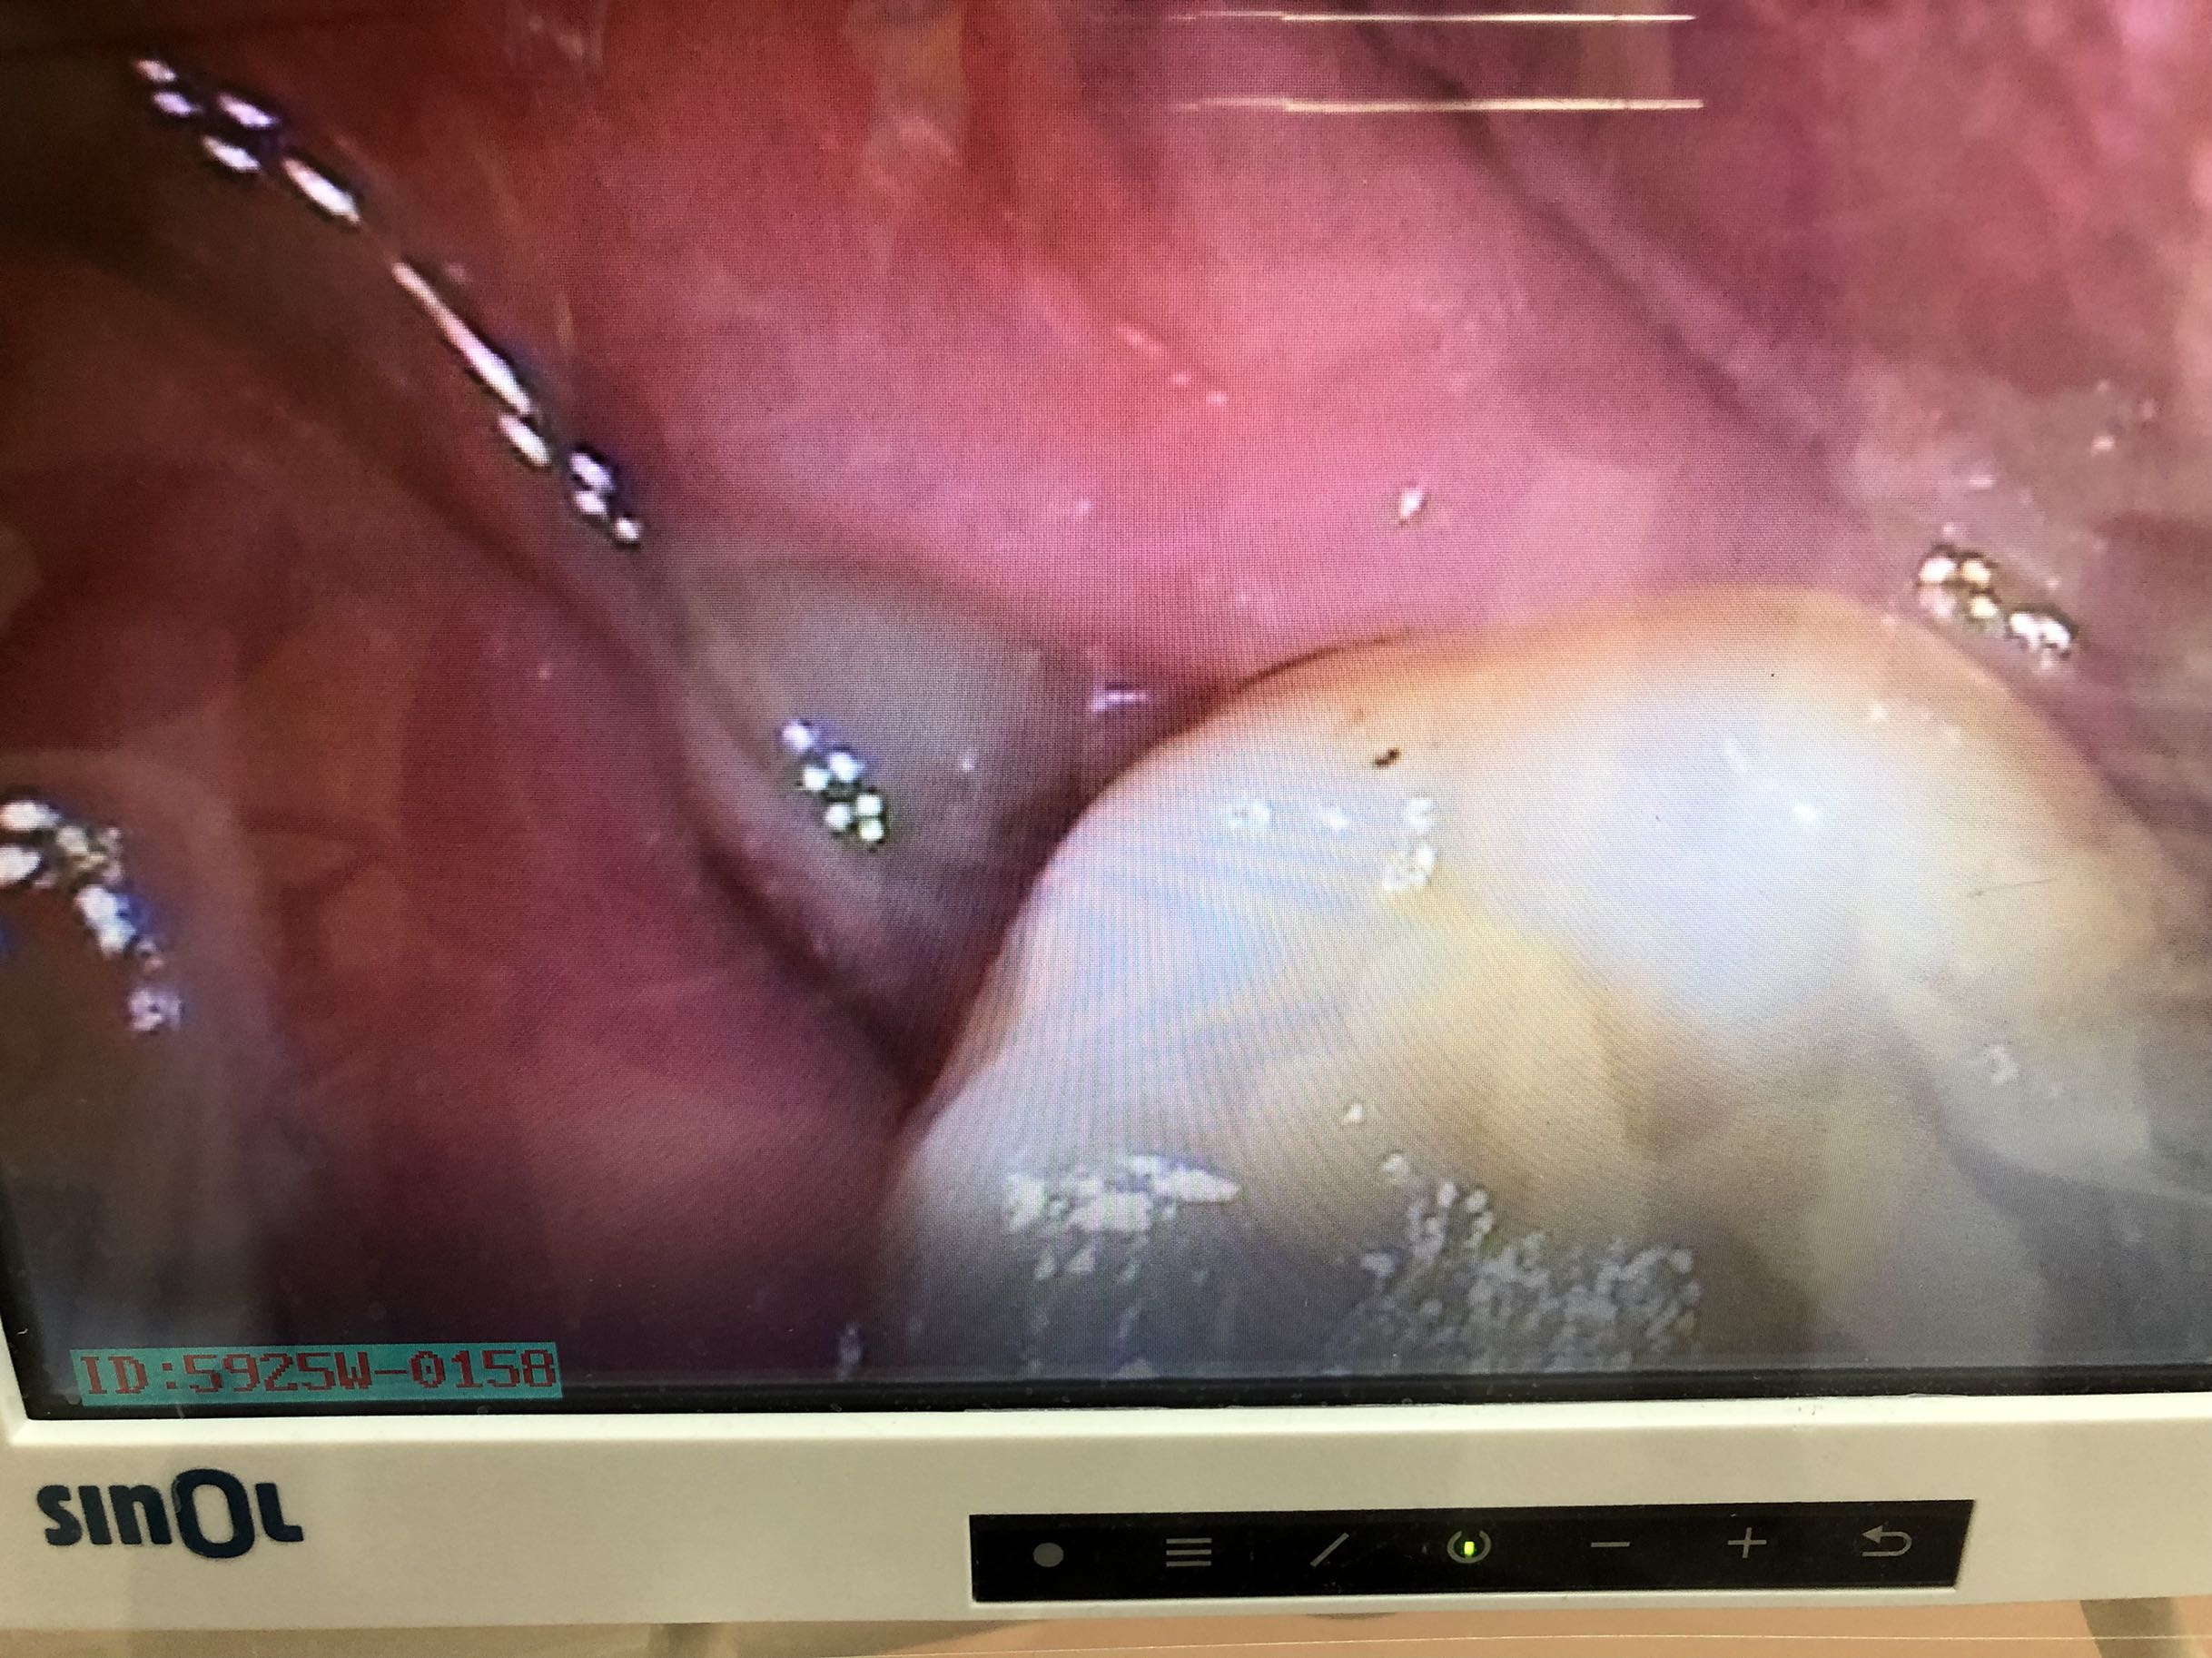

查体:48近中低位埋伏阻生,牙体露出少许,叩-,无松动,冠周牙龈无明显红肿,无压痛,开口正常。 辅助检查:曲片示48近中低位水平阻生,根尖近下颌神经管,根尖无明显暗影。

诊断:48低位水平阻生 治疗方案:建议拔除48,告知注意事项及风险,签知情同意书。 治疗:48局麻下(利多卡因,阻滞,4ml,碧蓝,浸润,0.8ml),切开,翻瓣,高速反角手机去除近中阻力,然后拔除余下牙根,清理牙槽窝,填塞止血海绵,缝合,棉球压迫止血,冰敷,一周拆线,全身抗炎,交待术后注意事项…,不适随诊。